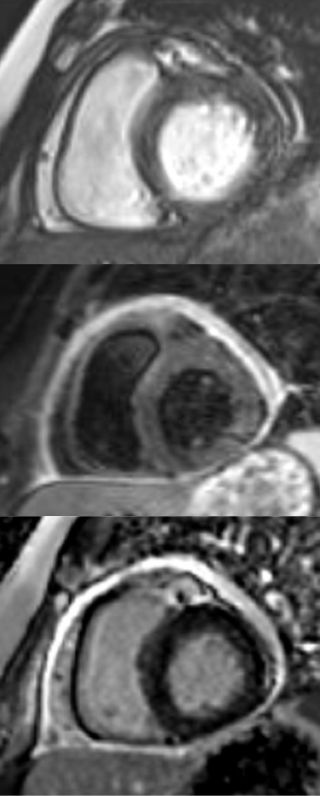

✨ Beautiful #CMR pictures. Young patient with new chest pain. SSFP, T2W, and LGE.

#NorthwellHealth #cardiosky